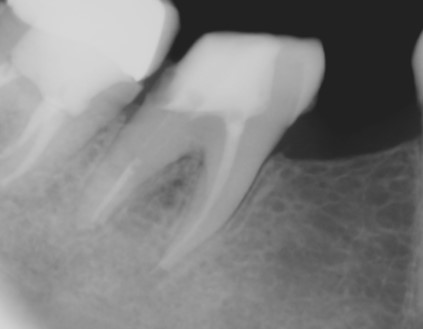

- Unhealthy pulp is removed. The length of the root canal is determined with the help of Electronic Apex locators as well as radiographs. The canals are then cleaned, enlarged and shaped with special caliberated instruments and disinfecting solutions.

- Periodic Radiographs (X rays) using digital RVG are taken during the treatment.

- Once the tooth is free of infection, the tooth is filled with a special root canal filling material like gutta percha and the access previously opened is sealed permanently with a Core filling.